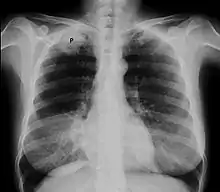

Chest X-ray showing a Pancoast tumor (labeled as P, non-small cell lung carcinoma, right lung), from a 47-year-old female smoker.

Diagnosis of a Pancoast tumor can be difficult in the early stages to the similarity of its symptoms with other conditions such as arthritis, with shoulder pain being one of the only symptoms that might indicate further imaging for a patient.[14] Though a chest x-ray is a good screening test and might be the first mode of imaging used, they are not easily seen during the early stages of the disease due to their size and location in the chest.[15]

Following the initial imaging, a CT scan or MRI is preferred since both can provide more details and information such as size, lymph node involvement and other areas of invasion, such as vascular involvement.[15][10]